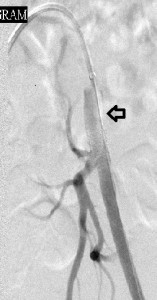

I present here a young woman whose primary care physician referred to me because of acute pain in her left great toe that was associated with discoloration. Her left common femoral pulse was diminished on examination and its waveform abnormal on arterial Doppler sonography. The image to the far left of the reader shows a focal filling defect of the distal left common iliac artery with sharp margins between its upper and distal surfaces and the vessel lumen, a calcified plaque from which a small embolus may have arisen. The rest of her angiography was normal. The middle image shows the deployment of a short balloon-expandable stent across the filling defect, while the image to the reader’s right is the post-intervention study that shows restoration of normal blood flow through the left iliac channel. Her symptoms resolved and she returned to her primary care provider on aspirin, Plavix, and advice to quite smoking, while pursuing hypercoagulability workup with him.